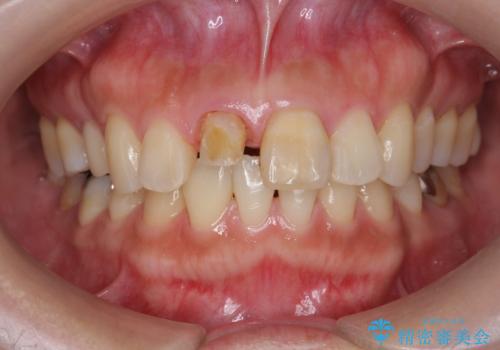

リアルな歯の色調にこだわるオールセラミッククラウン治療

- 歯の神経を除去したのちの、変色の改善を希望され来院されました。

再度根管治療を行ったのちの、オールセラミッククラン治療を計画します。

色調の再現に優れるオールセラミッククラウン スペシャルプランでの治療を希望されました。(保証5年間)

天然歯を再現したリアルな仕上がりに満足いただくことができました。

オールセラミッククラウン スペシャルプランは細やかな色調の再現に優れ、目立つ前歯の審美的な仕上がりがより達成されやすいプランです。